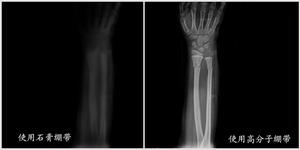

臨床試驗證明,達到一定的固定強度,矯形高分子繃帶用量僅是石膏繃帶重量的1/5、厚度的1/3,最大限度減輕人體活動的負擔。透X線

使用矯形高分子繃帶固定後,能夠清晰的觀察到接骨癒合情況,為手術的準確性和完美性提供了保證。